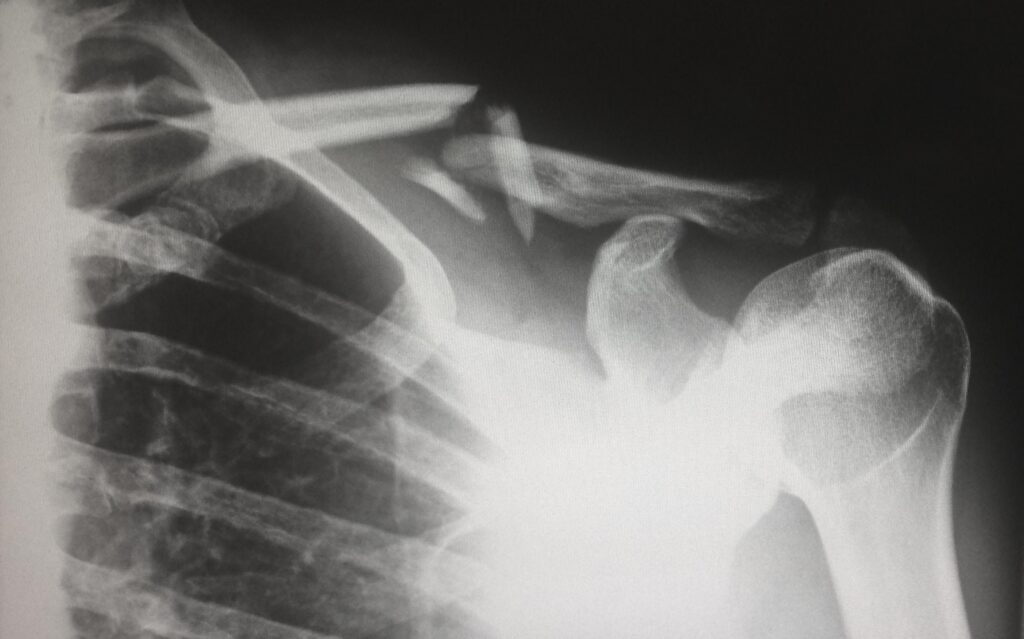

In 2002, Mr. Camp injured his shoulder while working on a job in Maryland. Although Mr. Camp immediately began compensation proceedings with the Maryland Workers’ Compensation Commission, he did not seek treatment from Dr. DiGrado until 2005. Dr. DiGrado performed two shoulder surgeries on Mr. Camp. The first surgery took place in January 2010, followed by a second surgery in March 2011. At this point, Mr. Camp had little improvement of his injuries and was aware that Dr. DiGrado performed his surgeries negligently. However, Mr. Camp did not file a lawsuit against Dr. DiGrado and the insurance company until 2015, after the statute of limitations had expired for his personal injury medical malpractice claim. Therefore, the district court dismissed Mr. Camp’s claims against Dr. DiGrado and the insurance company for failure to state a claim within the statutory period. Mr. Camp subsequently appealed to the Fifth Circuit Court of Louisiana, which ultimately affirmed the district court ruling and dismissed Mr. Camp’s claim because he did not file his claim more than three years after he ceased treatment with Dr. DiGrado. See Camp v. Digrado, 216 So. 3d 1055 (La. Ct. App. 2016).